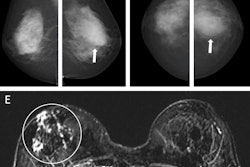

Images depict a 65-year-old patient with contralateral second breast cancer 6.3 years after right mastectomy. (A) Left craniocaudal and (B) mediolateral oblique mammograms assessed as benign. (C) The AI algorithm outlined a lesion with a score of 31 on the craniocaudal view. (D) A supplemental axial ultrasound scan, which was obtained on the same day as the mammogram, shows an irregular hypoechoic mass (arrows) in the left upper central breast. (E) Preoperative sagittal contrast-enhanced T1-weighted MRI scan shows the corresponding enhancing mass (arrow) in the left upper center. The mass was proven to be ductal carcinoma in situ.RSNA